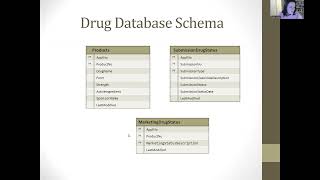

Computer Aided Drug Design Tutorial Website by Abdusemi Abduweli